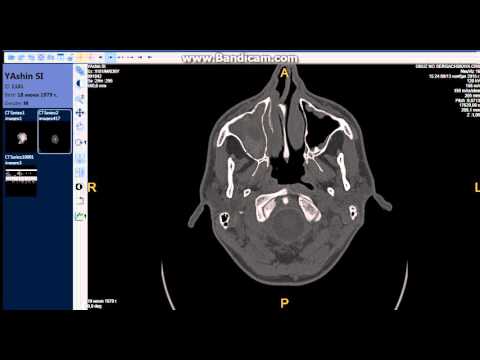

Рентгенограмма приносовых синусов.

Рентген пазух носа дает возможность оценить степень пневматезации синусов и других анатомических структур области носа. Также благодаря снимку можно точно дифференцировать заболевание (скопление жидкости, новообразование, киста или стороннее тело) и узнать точнее локализацию патологического процесса.

Расшифровывая снимок пациента с синуситом, можно сразу же провести более детальную дифференциальную диагностику, согласно его локализации и распространенности.